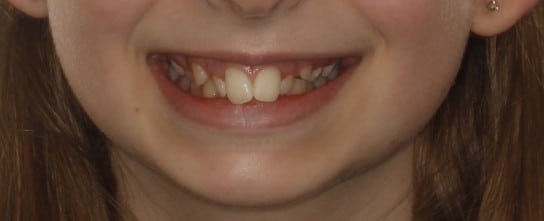

Phase I treatment with an Expander and Invisalign aligners

Phase I treatment with an Expander and Invisalign aligners to create space for permanent teethÂ